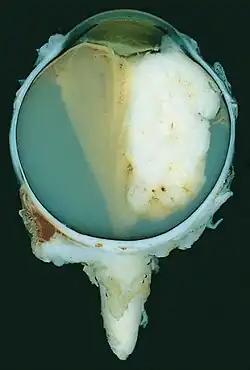

A pathology specimen of a retinoblastoma tumor from an enucleated eye of a 3-year-old female | |

Gross and microscopic appearances of retinoblastoma are identical in both hereditary and sporadic types. Macroscopically, viable tumor cells are found near blood vessels, while zones of necrosis are found in relatively avascular areas. Microscopically, both undifferentiated and differentiated elements may be present. Undifferentiated elements appear as collections of small, round cells with hyperchromatic nuclei; differentiated elements include Flexner-Wintersteiner rosettes, Homer Wright rosettes,[31] and fleurettes from photoreceptor differentiation.[32]

Large exophytic white tumor with foci of calcification producing total exudative retinal detachment